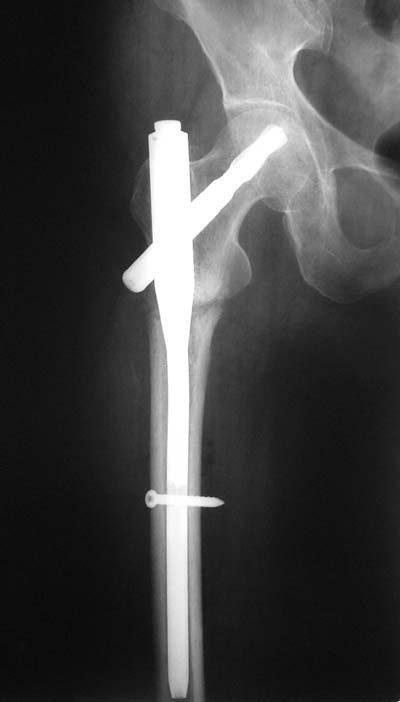

Да? Качество рентгенограмм конечно неочень, но ведь это нестабильный перелом 31.А2.2, не так ли?

Не думаю так. см вложение.

> Не думаю так. см вложение.

Для такого перелома вполне может быть использован диафизарный штифт, который отечественного производства я даже боюсь считать во сколько раз дешевле... Недавно несколько примеров я закидывал.